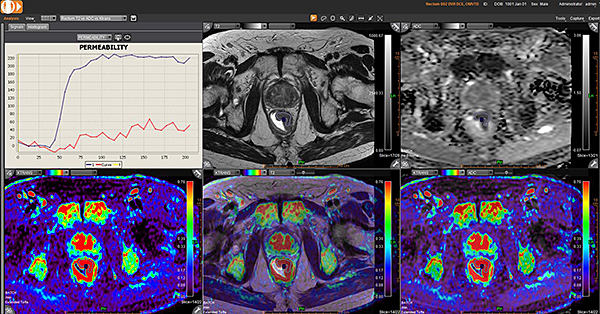

ОНКОЛОГІЧНІ ПАКЕТИ